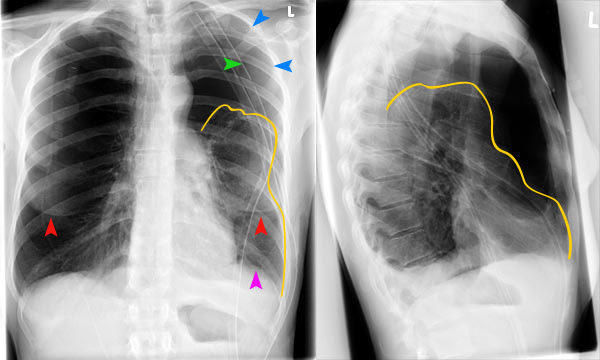

- рентген легких в двух проекциях: фронтальной и боковой;

При осмотре больного с плевритом легких видна асимметрия грудной клетки, больная часть отстает в акте дыхания. При большом скоплении выпота может наблюдаться синюшность кожных покровов, так как нарушается кровоснабжение в шейных венах из-за сдавления. Больная сторона грудной клетки выглядит объемней.

При перкуссии отмечается ослабление перкуторного звука, причем верхняя граница представляет собой косую линию-Дамуазо, которая хороша видна на рентгенографии. При выслушивании легких фонендоскопом отчетливо слышен шум трения плевры, он похож на скрип снега. Дыхание в местах скопления жидкости резко ослаблено.

На рентгенографии симптомы выпотного плеврита легких отображаются как интенсивное однородное затемнение в нижних долях органа. Высокое стояние диафрагмы наблюдается при небольшом скоплении жидкости. Средостение смещено к здоровому легкому. При выполнении снимка в латеропозиции (больной ложится на бок) происходит горизонтальное смещение экссудата.